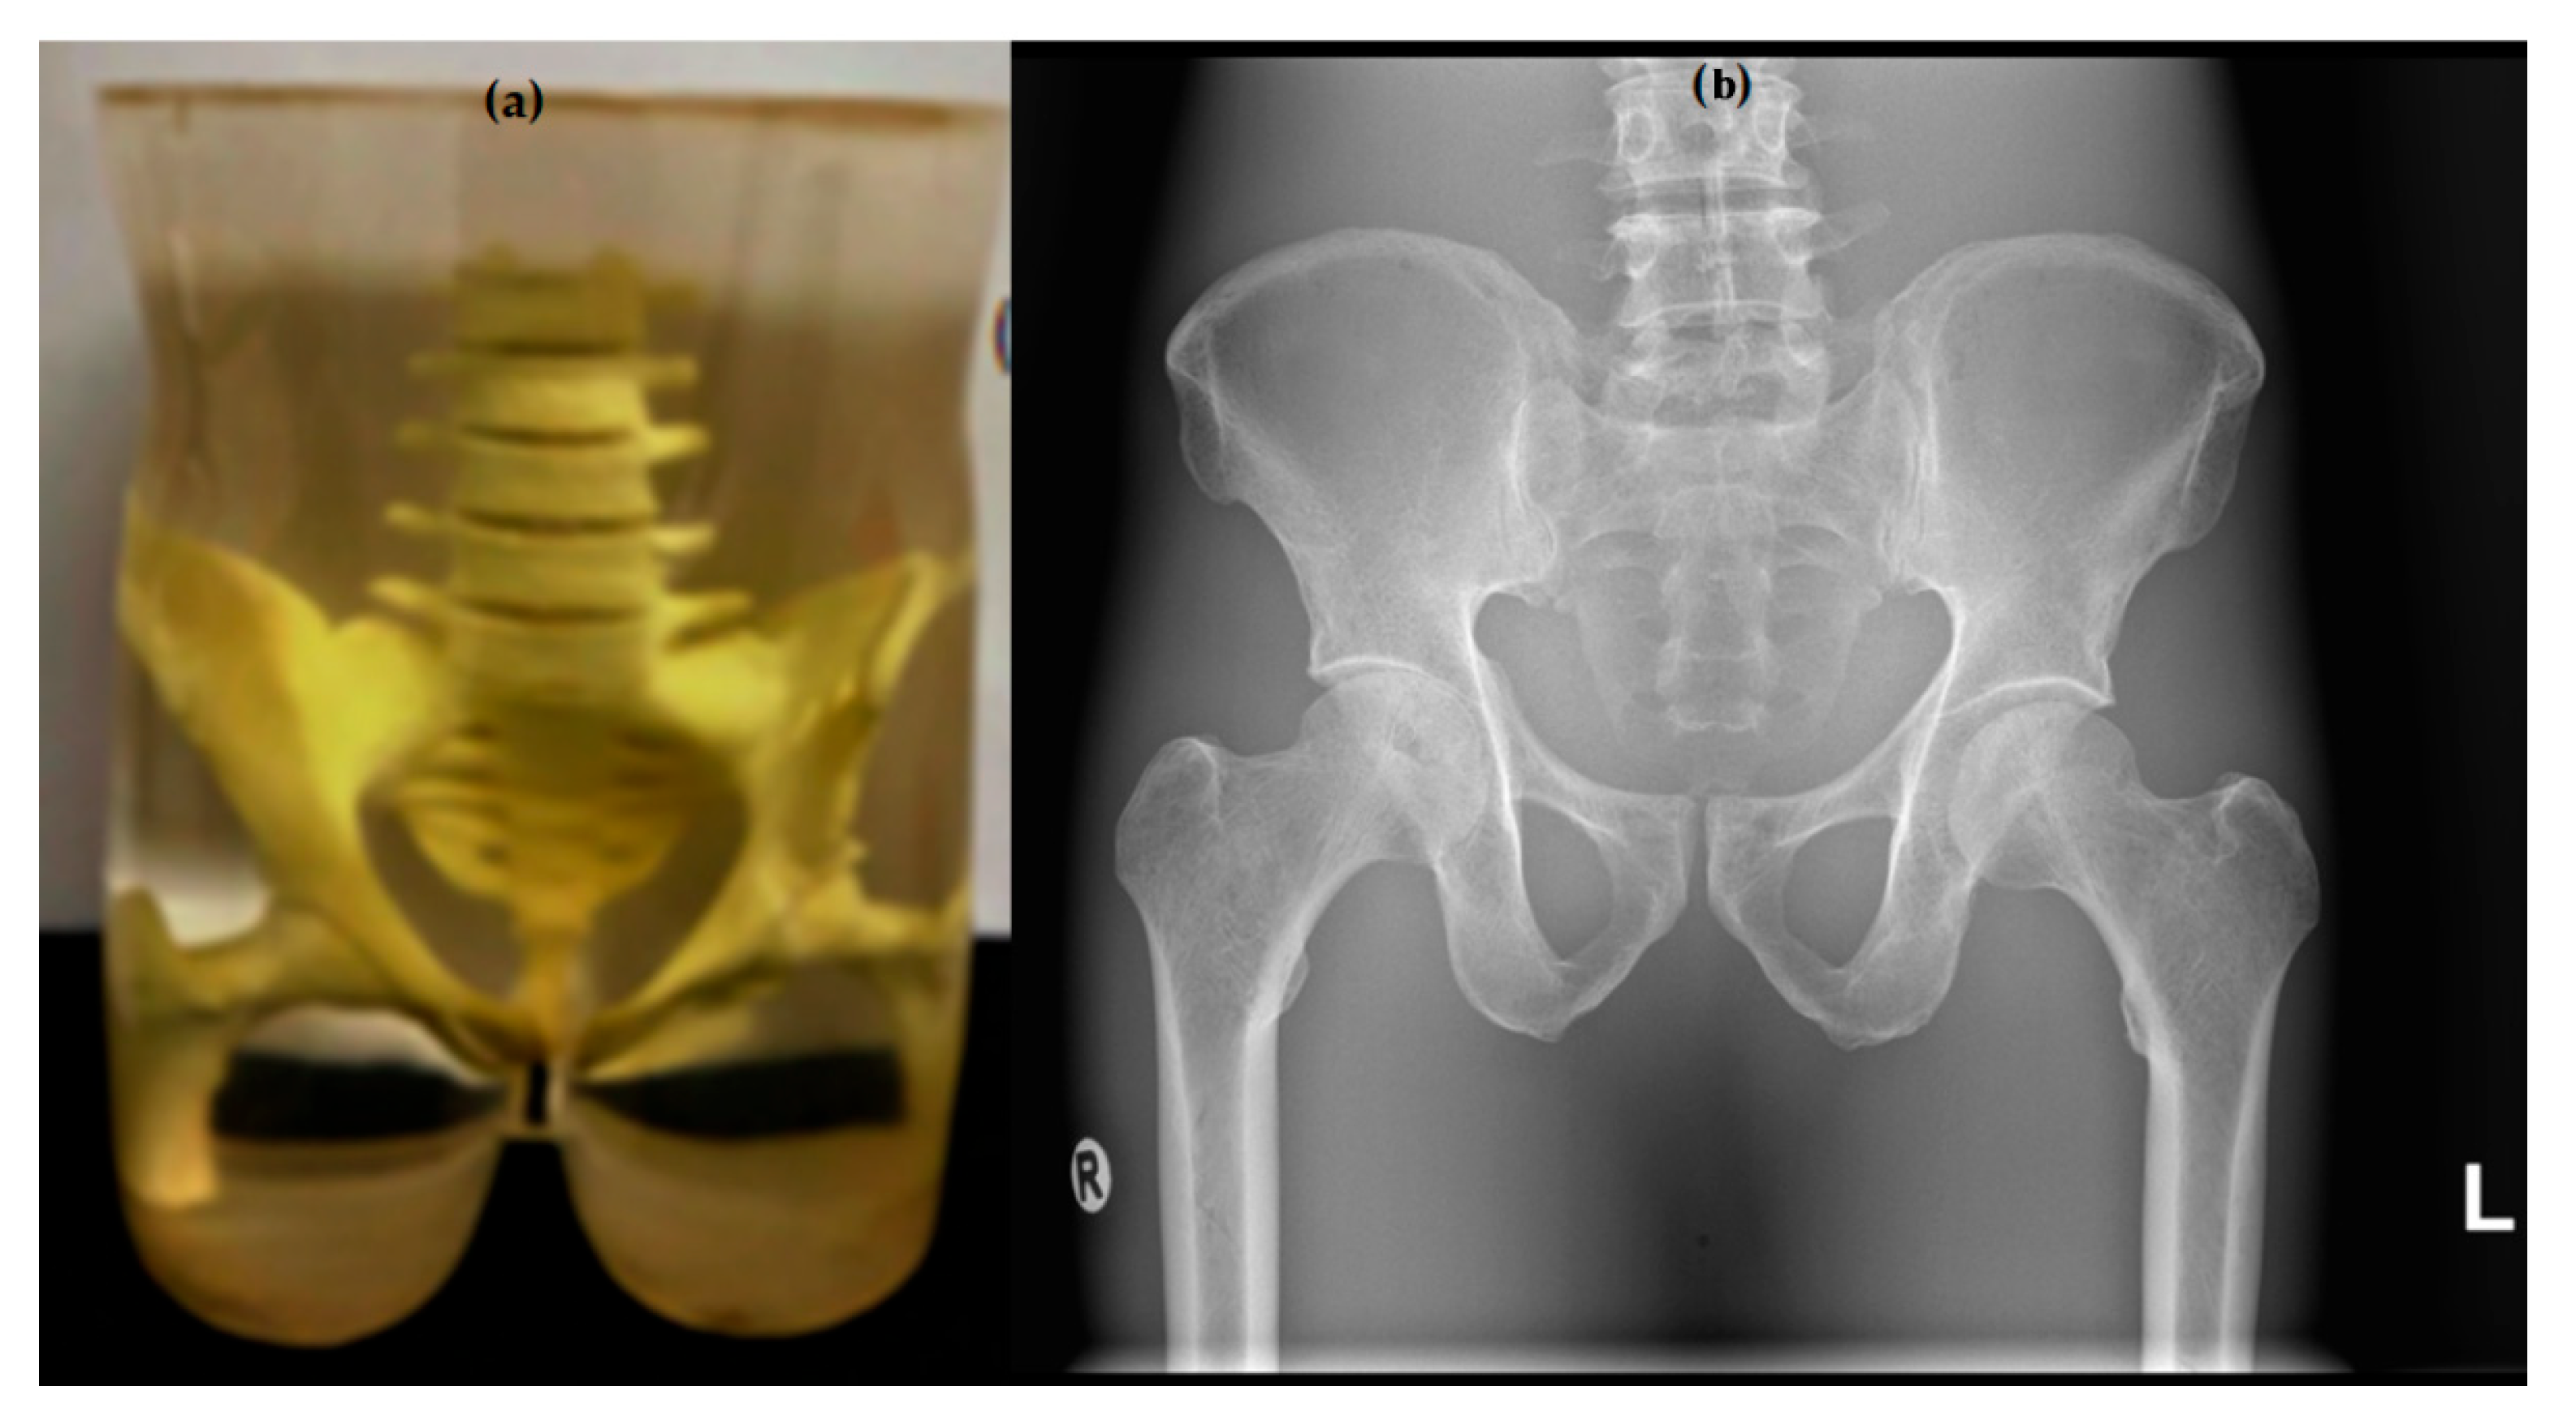

2.1. Protocol Settings and Image Acquisition